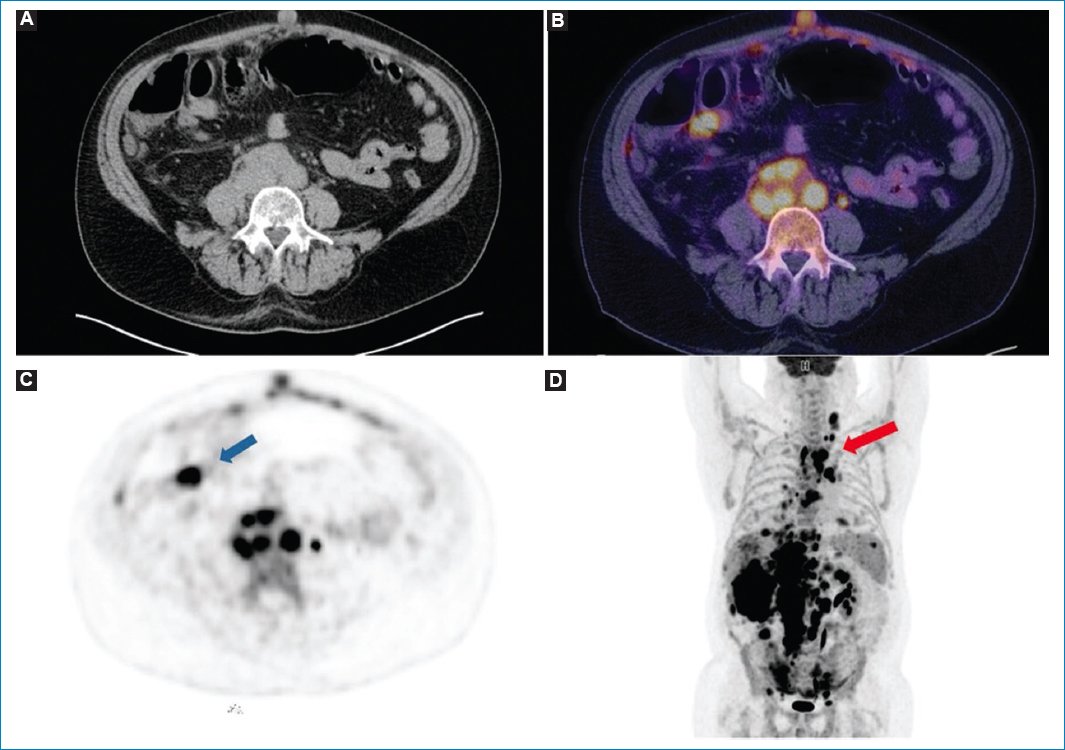

• –Un patrón nodular, donde el hipermetabolismo se observa en relación con las masas y los nódulos peritoneales (Figs. 47)

• –Un patrón difuso, con avidez por la 18F-FDG en forma difusa por el omento mayor y la superficie peritoneal (Figs. 811)

Figura 4. Mujer de 49 años con diagnóstico de linfoma no Hodgkin y LP. TC sin contraste endovenoso en imagen axial (A) que muestra patrón de engrosamiento nodular del peritoneo y adenopatías retroperitoneales. Fusión PET-TC (B) y MIP (C), cortes axiales, que demuestran el hipermetabolismo de los nódulos peritoneales y de las imágenes ganglionares (flecha).

Figura 5. Paciente con diagnóstico de linfoma no Hodgkin y LP. Imágenes coronales de TC (A), fusión PET-TC (B) y MIP (C), en las que se objetiva el compromiso nodular hipermetabólico del peritoneo (flecha).

Figura 6. Varón de 74 años con diagnóstico de linfoma no Hodgkin difuso de células B en recaída, con LP. Imágenes axiales de TC (A) y fusión PET-TC (B) que evidencian engrosamiento nodular del peritoneo y de la fascia pararrenal anterior, con aumento de consumo de 18F-FDG (flecha).

Figura 7. Varón de 65 años con diagnóstico de linfoma difuso de células B grandes y LP. Imágenes de TC (A), fusión PET-TC (B) y MIP (C y D) en las que se puede observar el patrón nodular hipermetabólico del peritoneo (flecha azul) y las adenomegalias en múltiples lugares (flecha roja).